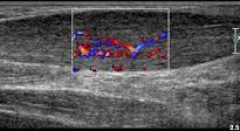

Patologiska senor

Vilket är det bästa sättet att belasta patologiska senor? Jag länkade till mitt blogginlägg med min handledare (Dr. Peter Malliaras) i förra inlägget. Tänkte att jag översätter det till svenska. Har uppdaterat det något med lite egna tankar på vissa ställen. Det behandlar alltså frågeställningen – Vilket är det bästa sättet att belasta en … Mer Patologiska senor